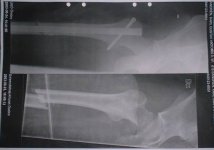

NoicE skrev:happ så här såg det ut

rainman skrev:Ser ut som det kommer vara riktigt skönt när dom ska dra ut den![]()

schrunken skrev:Fattar inte hur dom ska få ut den, då måste dom ju ta isär benet igenEller har dom fixat några snabbfästen, typ "plug in"

Mcbudet skrev:Samma väg som det kom in! genom höften! och det är MYCKET våld som behövs!![]()

Maverick skrev:hur mkt fick du betala för röntgenbilderna?? e jävligt sugen på att köpa ett par själv sen.. jag har bara fått se några av mina bilder.. men av dom jag fick se fanns de ingen bild som hade me hela lårbenet.. vilket jag tyckte var lite synd.. fast o andra sidan har jag typ bara sett 10 bilder..

Men du har väl oxå typ två stoppskruvar nere vid knät eller??